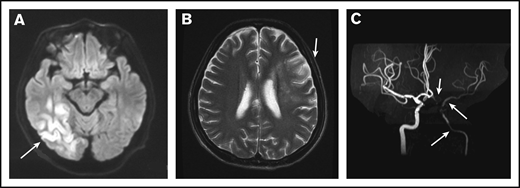

Among 41 IS cases, 19 (46.3%) were multifocal, including 12 bilateral and 7 unilateral. Cerebral vessels were evaluated in only 8 patients via magnetic resonance angiography (MRA) or computed tomography angiography (CTA) (Figure 2A-C). Seven (87.5%) of 8 patients were documented to have cerebral vasculopathy; 3 patients were shown to have multiple and bilateral cerebral artery stenosis or occlusion, including the internal carotid artery, 2 with unilateral internal carotid artery stenosis, 1 with unilateral middle cerebral artery stenosis, and 1 with unilateral posterior cerebral artery stenosis. Cerebral venous sinus thrombosis was demonstrated in 1 patient.

MRI and MRA for a patient with POEMS syndrome and IS. (A) MRI of the brain showed a cerebral infarction of the right temporal occipital lobe (white arrow). (B) A second MRI showed a new focal lesion of cerebral infarction near the left centrum semiovale 1 month later (white arrow). (C) MRA showed severe stenosis of the left intracranial internal carotid artery, left middle cerebral artery, and left anterior artery (white arrows).

The pathophysiologic mechanism underlying IS in patients with POEMS syndrome has not been elucidated. Ninety-three percent (38 of 41) of IS events occurred before or immediately after the diagnosis of POEMS symptoms, suggesting that active disease may be an indicator for IS susceptibility.6 There are several possible explanations for the occurrence of IS in our patients. First, hyperfibrinogenemia in our cohort and in other reports22-26 is believed to trigger a hypercoagulative state. Thrombocytosis,4,6 polycythemia,4,27 bone marrow plasma cell proliferation,6 and high levels of circulating proinflammatory cytokines such as VEGF10,22 have also been reported to increase the risk of IS; however, our study showed that these factors were identical in IS and non-IS patients. Second, large vessel stenosis or occlusions or structural anomalies confirmed by MRA or CTA, especially in patients with no known risk factors for atherosclerosis, is thought to be the cause of stroke. In our study, 7 of 8 patients who underwent MRA had internal carotid artery and/or other proximal intracranial artery stenosis or occlusion, similar to that reported by Dupont et al.6 Yaghi et al28 described 1 patient with POEMS syndrome and recurrent stroke whose temporal artery biopsies were negative for an inflammatory process but showed thickening of blood vessels, which distinguishes vasculopathy from vasculitis and atherosclerosis. Angiogenesis within the adventitia of vessel walls induced by VEGF also plays an important role in the pathogenesis of chronic inflammation of vessel walls.22,29-31